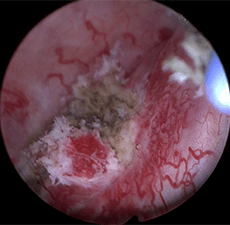

Patient underwent left percutaneous resection followed by 6 once-weekly antegrade instillations of Jelmyto for the treatment of residual disease.

3-month surveillance cystoscopy and ureteroscopy were negative.